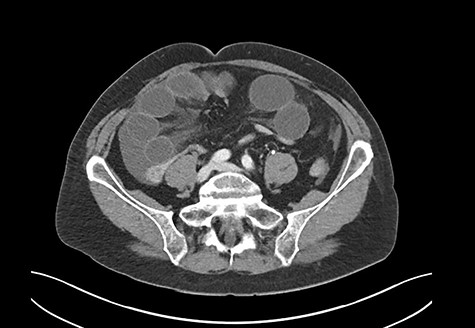

A 69-year-old woman was referred to our institution due to clinical signs of acute abdomen. She reported diffuse abdominal pain without an identifiable trigger, associated with recurrent vomiting. The patient had no history of abdominal operations, took no medications, and never experienced a similar episode before. A computed tomography (CT) scan revealed small bowel ileus (Fig. 1). The radiologist suspected a mechanical obstruction.

CT scan: severe mechanical obstruction of the small intestine caused probably by adhesions.